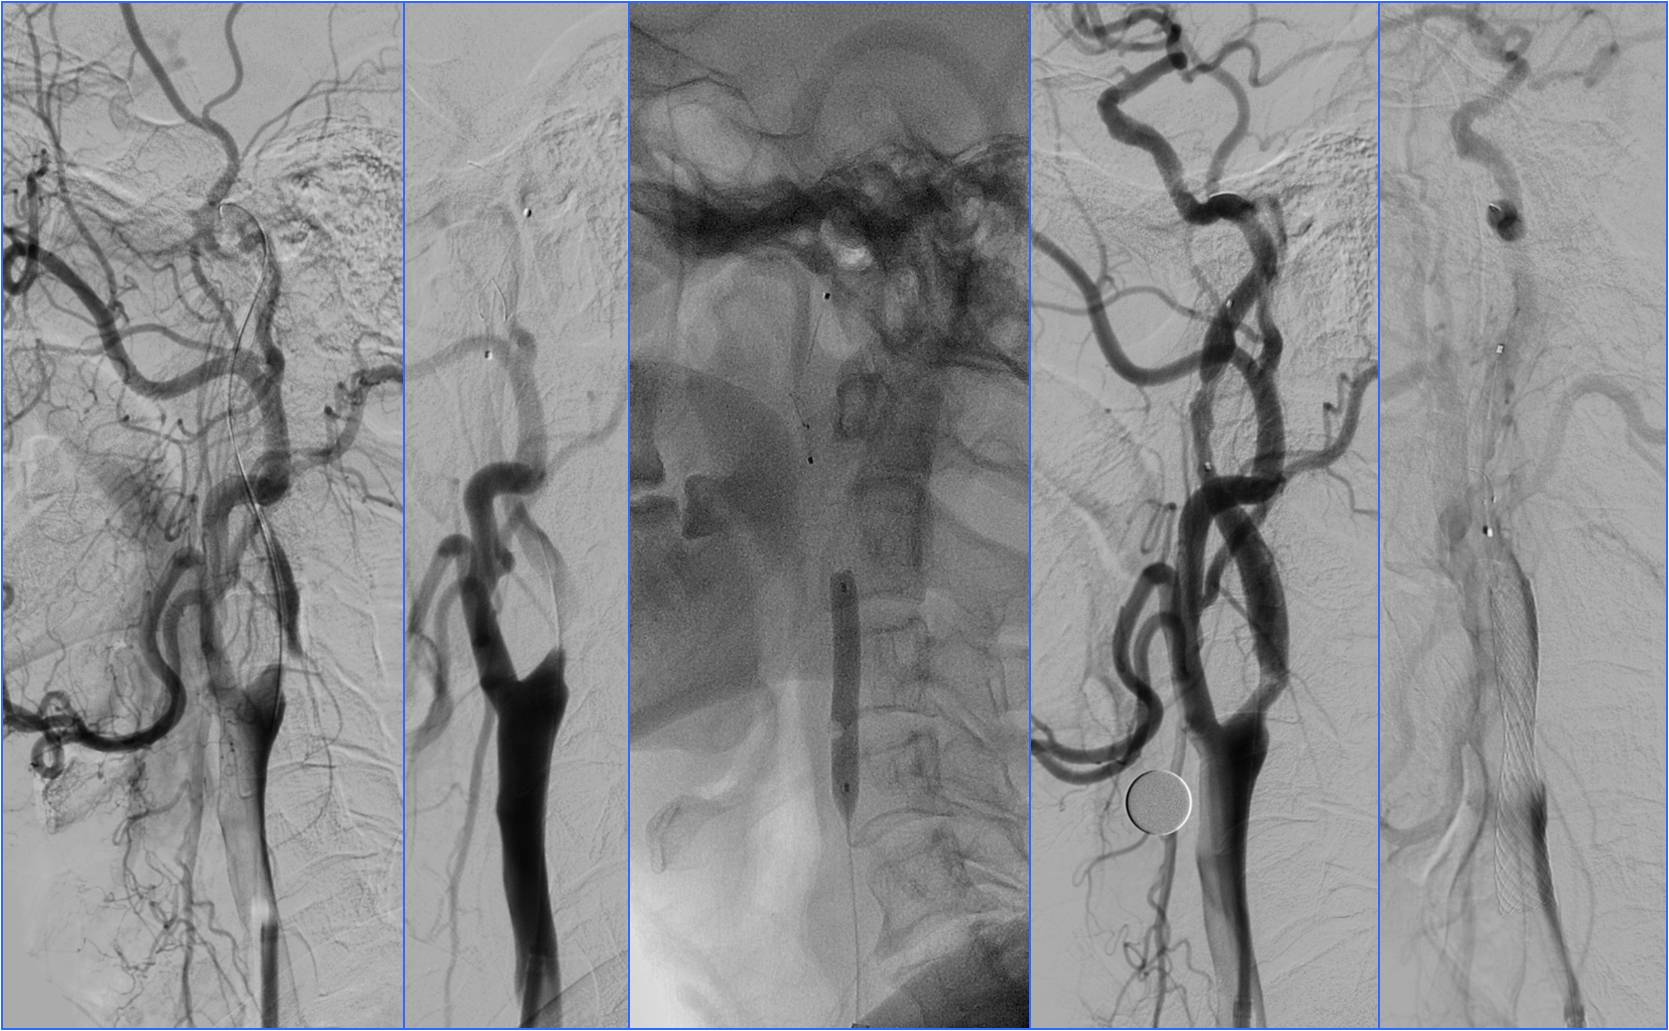

》DSA见基底动脉闭塞,Solitaire支架取栓后见基底动脉重度狭窄,Gateway球囊扩张,置入Wingspan支架。

》术后24h完全恢复,NIHSS评分0分。

▼13:49DSA

▼支架取栓后基底动脉残余重度狭窄

▼基底动脉支架置入术

▼4天后复查MRA

Case4 基底动脉支架置入

》男,60岁。既往高血压病史。

》因“言语不清、右侧肢体无力1小时”于9:00到急诊就诊。

》查体:血压140/90mmHg。神志清,运动性失语,右侧肢体肌力3级,右侧巴氏征阳性。NIHSS评分6分。

》头CT检查未见出血(9:19)。

》9:50给阿替普酶静脉溶栓,5mg静推,余45mg持续泵入。

》半小时内患者症状完全缓解。

》11:00突发意识不清。

》11:11复查头CT。

》11:56头MRA。

》准备介入血管内治疗,患者症状自行缓解。后又加重,症状波动2次。

》13:22进入导管室行血管内治疗。行气管插管全身麻醉。